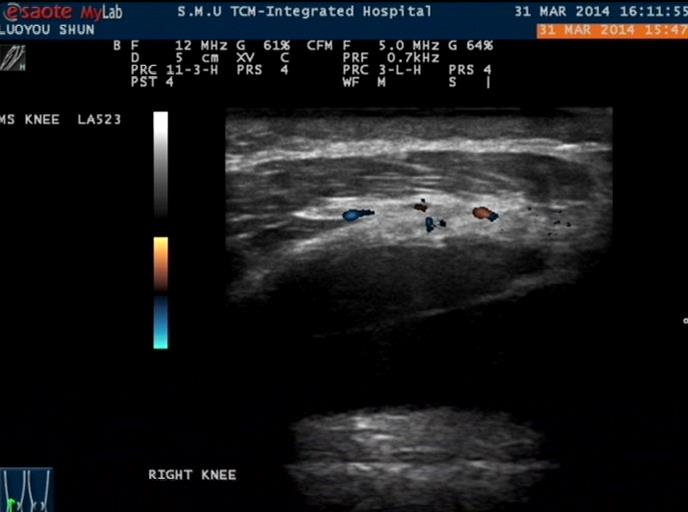

48岁的罗某,湖南衡阳市人,今年年初爬山后出现右膝关节红肿热痛,在湖南当地医院行右膝关节穿刺抽液抽出血性积液,行磁共振检查发现积液,诊断为“创伤性关节炎”,予止血、营养骨关节治疗无改善,为进一步治疗入住我科,行关节彩超检查提示“膝关节滑膜增生呈团块样,内见血流信号,股骨质局部破坏灶”,结合关节积液颜色,诊断为“色素沉着绒毛结节性滑膜炎”,予以免疫抑制抗炎止痛治疗,目前随诊病情无复发。